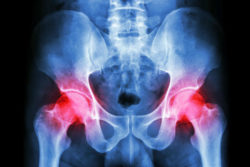

Kenneth claims that the Biomet M2a Magnum hip replacement is defective in its design, and its defect causes it to perform sub-optimally and do harm to patients who have been implanted with it. Allegedly, the device is made with a metal ball and a metal socket, as opposed to one metal and one plastic component or with a nonmetal liner, like many other hip implant systems.

The Biomet M2a Magnum hip replacement lawsuit claims that the M2a Magnum’s two metal components come into contact with one another in such a way that the metal pieces wear away on one another, causing metal pieces to fret into a patient’s body. This allegedly occurs when the two pieces of the device are not implanted at exactly the right angle, which allegedly is a very common occurrence when the device is installed.

The Zimmer hip lawsuit claims that the metal fragments fretting into a patient’s body can cause infection, tissue death in both bone and soft tissue, and can cause the levels of metal in a patient’s blood to rise to dangerous levels. This alleged design incompatibility may also cause the pieces to wear incorrectly, causing the device to perform sub-optimally and make movement difficult.